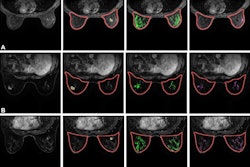

Examples of automatic fibroglandular tissue (FGT) segmentations on the precontrast (T1) non-fat saturated series and background parenchymal enhancement

(BPE) extent on the postcontrast (T2) series for four control participants. For each participant, the left image shows the automated whole-breast segmentation (green line) and FGT segmentation (purple shading). The right image shows the areas of enhancement (red shading) within the FGT, defined as all voxels with 20% or more enhancement from the precontrast to postcontrast series. For each series, the middle section is presented. Example images were selected randomly within four categories defined by quantitative FGT volume (Vol) and BPE extent, where “low” refers to participants with measures in the bottom tertile and “high” refers to participants with measures in the top tertile. (A) Low FGT volume and low BPE extent in a 50-year-old premenopausal control participant. (B) Low FGT volume and high BPE extent in a 50-year-old control participant with a history of bilateral oophorectomy. (C) High FGT volume and low BPE extent in a 39-year-old premenopausal control participant. (D) High FGT volume and high BPE extent in a 44-year-old premenopausal control participant. Images and caption courtesy of the RSNA.